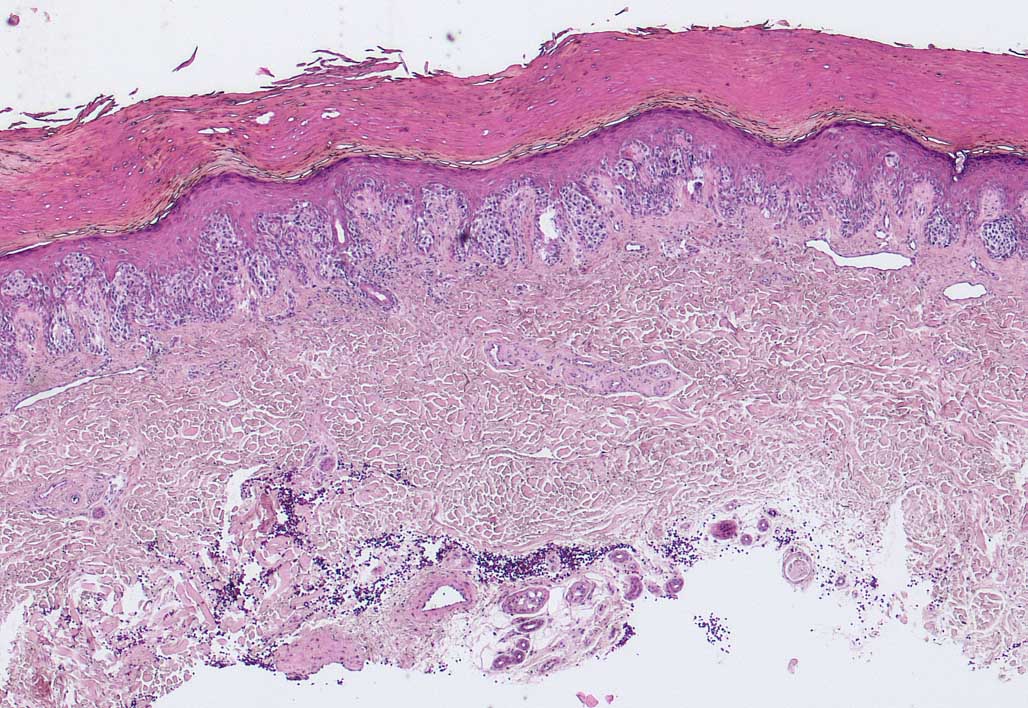

PathoPic ID 6733 - akrallentiginöses Melanom

akrallentiginöses Melanom

Haut, untere Extremität

Leistenhaut mit sehr dicker Hornschicht. Breite melanozytäre Läsion mit Überwiegen von Einzelzellen in lentiginöser Ausbreitung.

Unregelmässig pigmentierter 7mm grosser Tumor am rechten Grosszeh.

Histologie

25